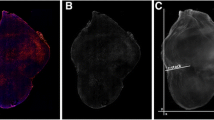

Four types of liposomes were prepared having membranes with different combinations of release (R) and adhesion (A) properties. The combinations were R−A−, R−A+, R+A−, and R+A+. These afford different penetrating properties into tissue. The liposomes were loaded with either carboxyfluorescein diacetate succinimidyl ester (CFDA-SE) or 225Ac. MDA-MB-231 spheroids were treated with the CFDA-SE-liposomes, harvested at different times, and the time-integrated CFDA-SE concentration at each radial position within the spheroid was determined. This was translated into mean 225Ac decays/cell versus radial position, uploaded to MIRDcell, and the surviving fraction of cells in spherical multicellular clusters was simulated. The MIRDcell-predicted surviving fractions were compared with experimental fractional-outgrowths of the spheroids following treatment with 225Ac-liposomes.